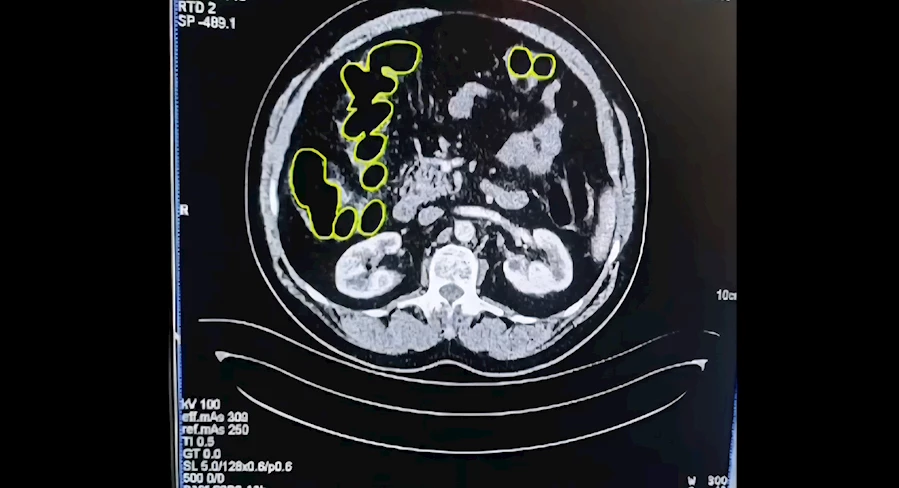

Şüphelilerin Kayseri Şehir Hastanesinde iç beden muayenesine alınırken, mide ve bağırsaklarında da çok miktarda kapsül şeklinde uyuşturucu olduğu değerlendirilen yabancı maddeler tespit edildi.